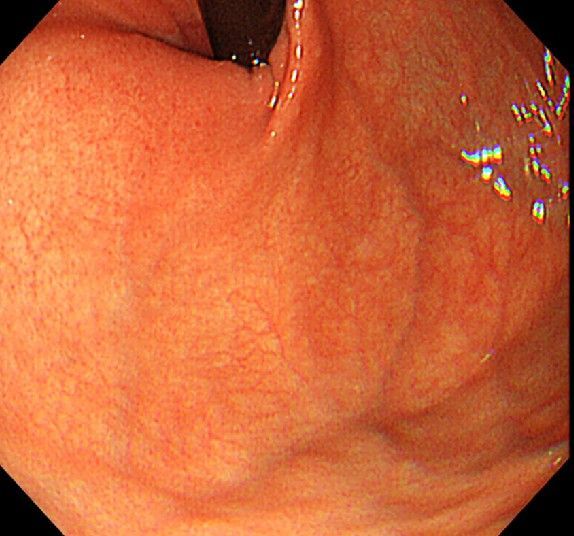

위 내시경을 찍었는데 위염 종류 사진을 알 수 있을까요? (사진 많습니다..)

한달 전 쯤에 소화불량과 속쓰림이 3개월 동안 약을 먹어도 낫지 않아 위 내시경을 찍었는데 위에 염증이 많이 있다는 이야기를 들었습니다...그런데 상태가 얼마나 안 좋은지 어떤 종류의 위염인지에 대해서는 물어봐도 안 알려주셔서 여기에라도 올려서 여쭈어봅니다... 제 상태가 얼마나 심각한 걸까요..

사진상으로 보아서는 정상에 가까운 점막상태이거나 약간의 표재성 위염이 있는 정도로 보입니다.

홍반성 위염이 있으며 경증의 역류성 식도염이 있습니다

위내시경상으로는 특이소견이 없다고 보셔도 됩니다